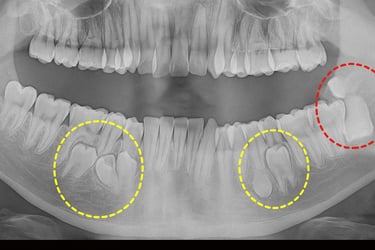

Q2. How do I know if I need wisdom tooth removal?

π If you have pain, swelling, gum infection, or misalignment, wisdom tooth extraction may be necessary.